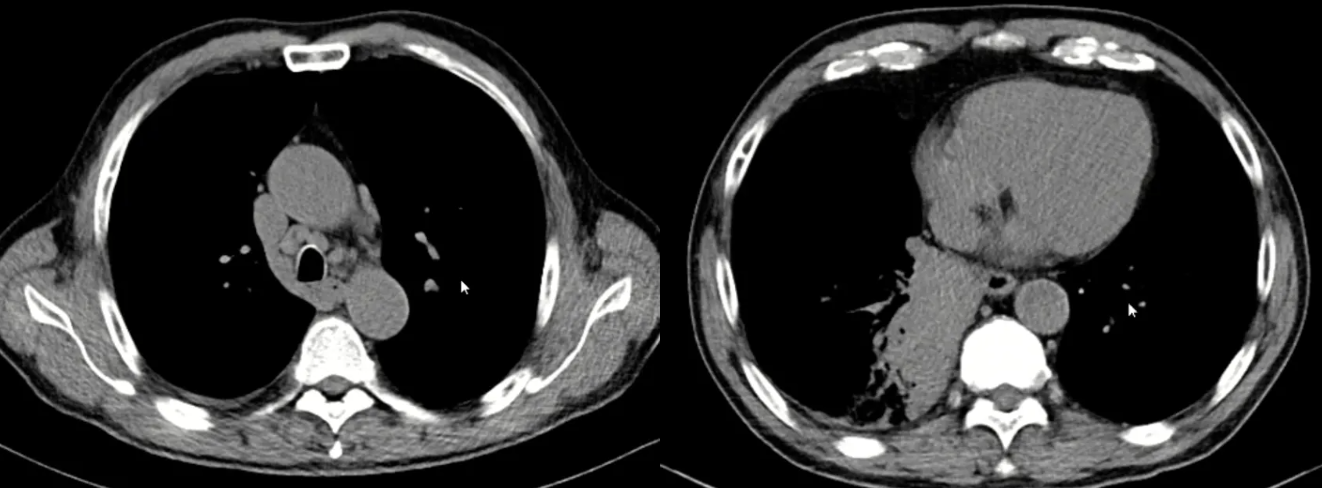

因目前气管镜病理无法明确诊断,建议患者行肺穿刺,但患方顾虑肺穿刺风险,要求先抗感染治疗以后观察。我们给予了为期三周的莫西沙星治疗。治疗结束后,于2025年7月22日复查胸部CT,这时的结果又让“感染”的假设落空了:肺部病灶与淋巴结大小较前无明显变化,右侧胸腔积液甚至稍有增多。

图2:抗炎治疗一个月后复查肺部CT

到这时,我们面临的临床鉴别诊断困境已十分明显。来总结一下患者的情况:患者为老年男性,重度吸烟史,影像学高度怀疑肺癌,但抗感染无效,且存在一个显著的血清学异常,IgG4升高。是两种疾病并存(肺癌合并某种导致IgG4升高的状态)吗?还是根本就不是肺癌?